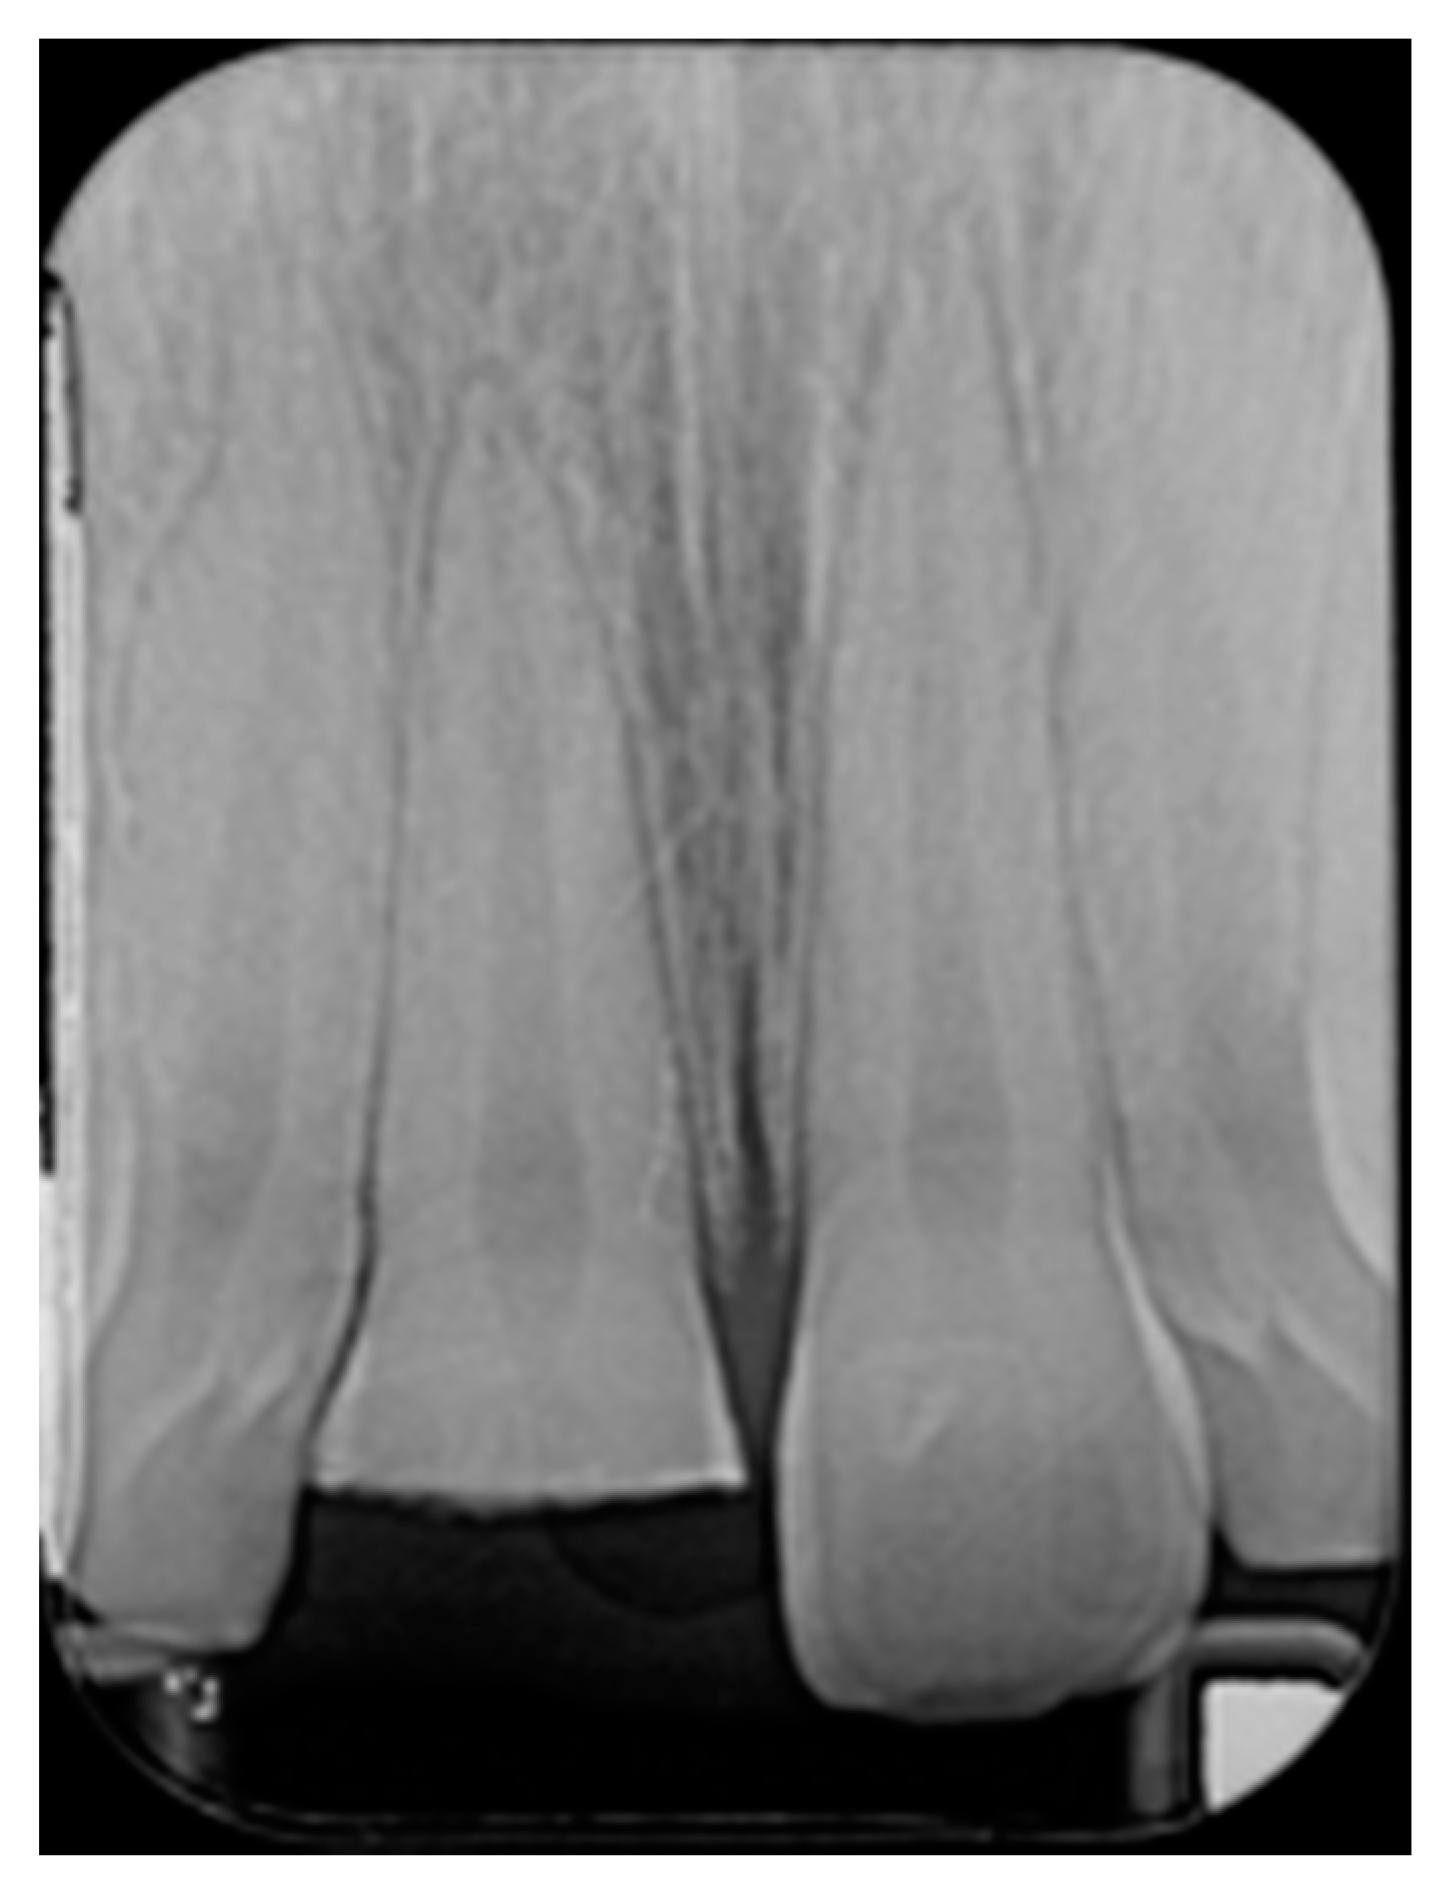

Figure 17.

One year post-operative x-ray. Reprinted from Restauri diretti nei settori anteriori, G. Paolone, S. Scolavino, © 2021, with permission from Quintessence Publishing Italy.

Finishing and polishing procedures were performed with a diamond bur (WL 268 014 Horico, Berlin, Germany), silicone points (Identoflex, Kerr, Bioggio, Switzerland) brushes (Jiffy Goat Air Brushes, Ultradent Products, South Jordan, UT, USA), and diamond pastes (Diamond Polish Mint, Ultradent Products, South Jordan, UT, USA) (Figure 13 and Figure 14). Satisfactory clinical and radiographic outcome was considered satisfactory at 3-months, 1-year, and 5-years post-operative (Figure 15, Figure 16, Figure 17, Figure 18 and Figure 19).